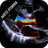

O principal objetivo deste aplicativo é ensinar as pessoas a calcular a área da válvula aórtica. A área da válvula aórtica é o principal fator na determinação da gravidade da estenose aórtica.

A área da válvula aórtica é medida com uma ferramenta usada para medir a distância entre a parede interna da aorta e a parede da o coração.